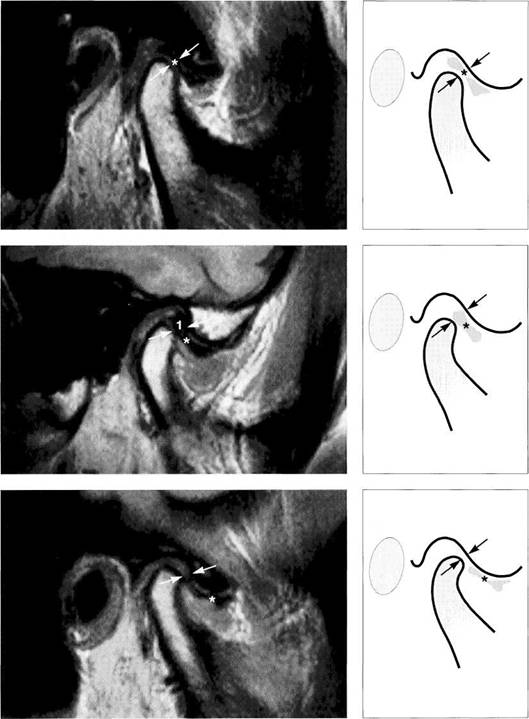

Physiological disk position

Under normal conditions, the pars intermedia (*) of the disk lies be­tween the anterosuperior curva­ture of the condyle and the articular protuberance (arrows). The posi­tion of the posterior border of the pars posterior relative to the vertex of the condyle varies according to the inclination of the protuberance and is therefore not a reliable pa­rameter.

The arrows in this schematic draw­ing mark the relative positions of the condyle and the pars interme­dia to one another.

Insidious disk displacement or a tendency to anterior disk displacement

The pars intermedia lies well in front of the shortest distance be­tween condyle and protuberance (arrows), but the pars posterior (1) still lies on the condyle. Clinically, there are no clicking sounds during jaw opening.

Right: Drawing of a joint with a ten­dency to anterior disk displace­ment. The arrows mark the discrep­ancy between pars intermedia and condyle.

Definite disk displacement

Left: Both the pars intermedia (*) and the posterior border of the pars posterior lie in front of the most anterosuperior curvature of the condyle (arrows). Unless this is a case of disk displacement without repositioning, a clicking sound will occur regularly during jaw opening.

Right: Schematic drawing of a defi­nite anterior disk displacement. The arrows mark the discrepancy between the pars intermedia and condyle.